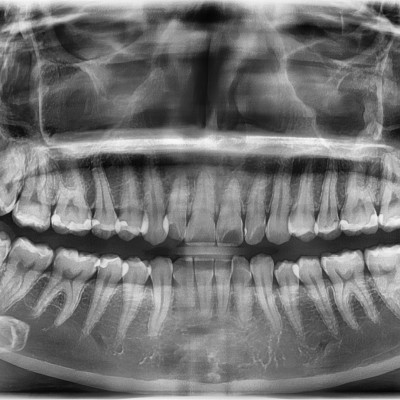

#28,38 사랑니 발치 #28,38 사랑니 발치 구강외과 전문의가 당일 발치했습니다.